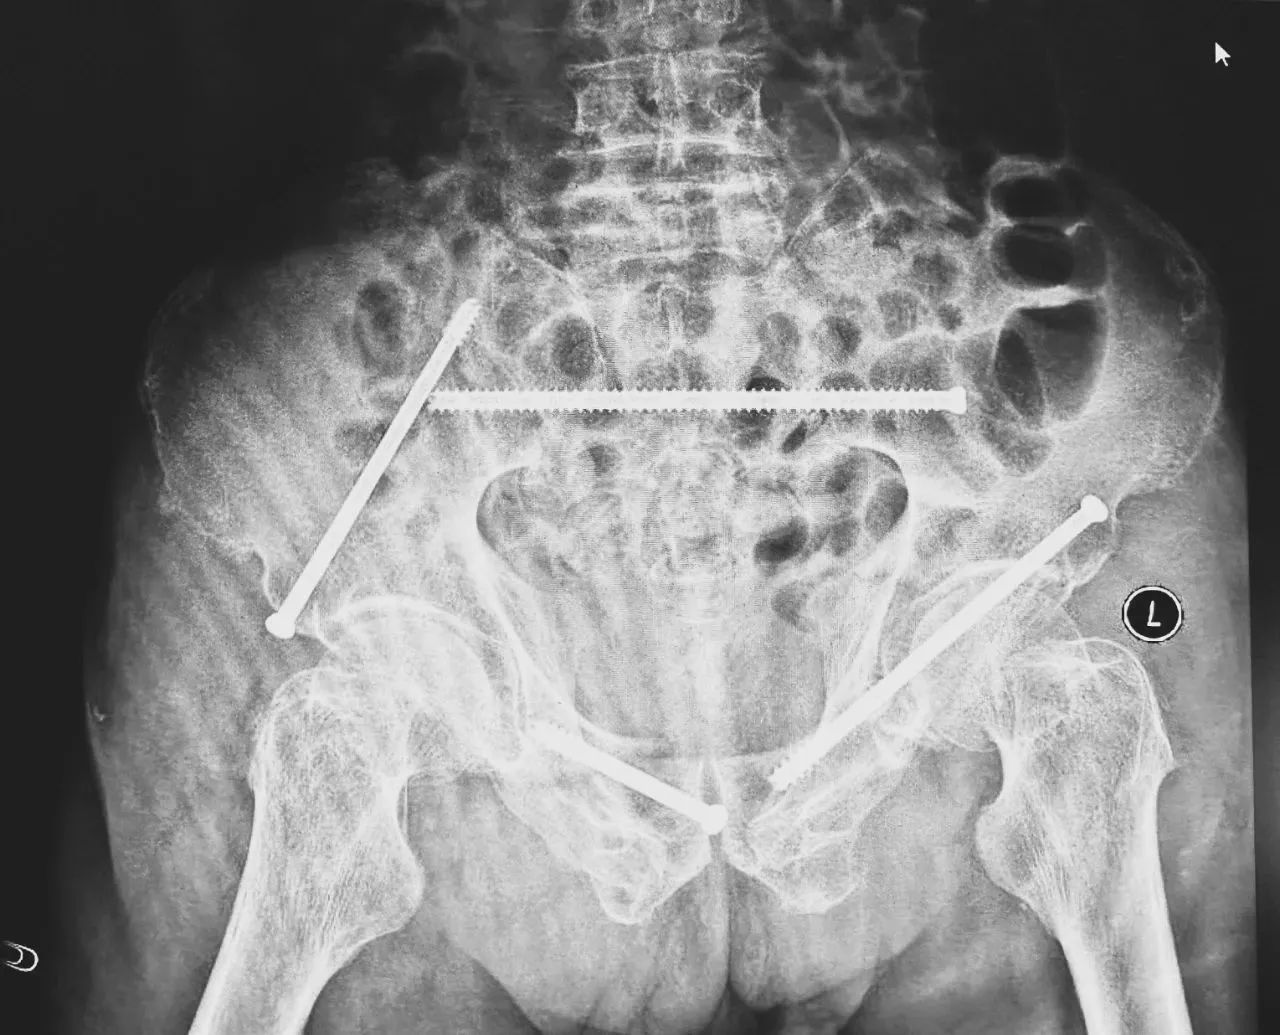

無(wú)影燈下,智能骨科團(tuán)隊(duì)將患者示蹤器,放在左側(cè)髂前上棘,使用術(shù)中三維影像設(shè)備獲取骨盆的三維圖像,掃描結(jié)果傳輸至機(jī)器人導(dǎo)航系統(tǒng),完成螺釘置入的位置和走形,并在機(jī)器人的引導(dǎo)下分別置入4枚通道螺釘。置入后再次進(jìn)行CT掃描驗(yàn)證,證實(shí)導(dǎo)針精確置入。

在骨科手術(shù)機(jī)器人毫米級(jí)精度的引導(dǎo)下,這項(xiàng)原本高難度、高風(fēng)險(xiǎn)的手術(shù)變得更加精準(zhǔn)高效。手術(shù)共計(jì)耗時(shí)1個(gè)半小時(shí),術(shù)中出血不到20毫升,每枚螺釘置入位置的切口長(zhǎng)度約1.5厘米,完美達(dá)到了預(yù)期。術(shù)后,王大爺安全返回病房。

術(shù)后第二天,醫(yī)生團(tuán)隊(duì)復(fù)查X片顯示螺釘植入位置非常滿(mǎn)意,骨折基本達(dá)到穩(wěn)定復(fù)位,同時(shí),復(fù)查的全血細(xì)胞計(jì)數(shù)中,血紅蛋白指數(shù)為102g/L。術(shù)后第三天,在智能骨科病房護(hù)理團(tuán)隊(duì)及康復(fù)師的指導(dǎo)和護(hù)理下,王大爺可以坐立在床上。術(shù)后第四天,王大爺迎來(lái)了出院日,“得虧有了這么先進(jìn)的醫(yī)療技術(shù),讓我還能下地行走,謝謝你們!”

螺釘植入位置非常滿(mǎn)意